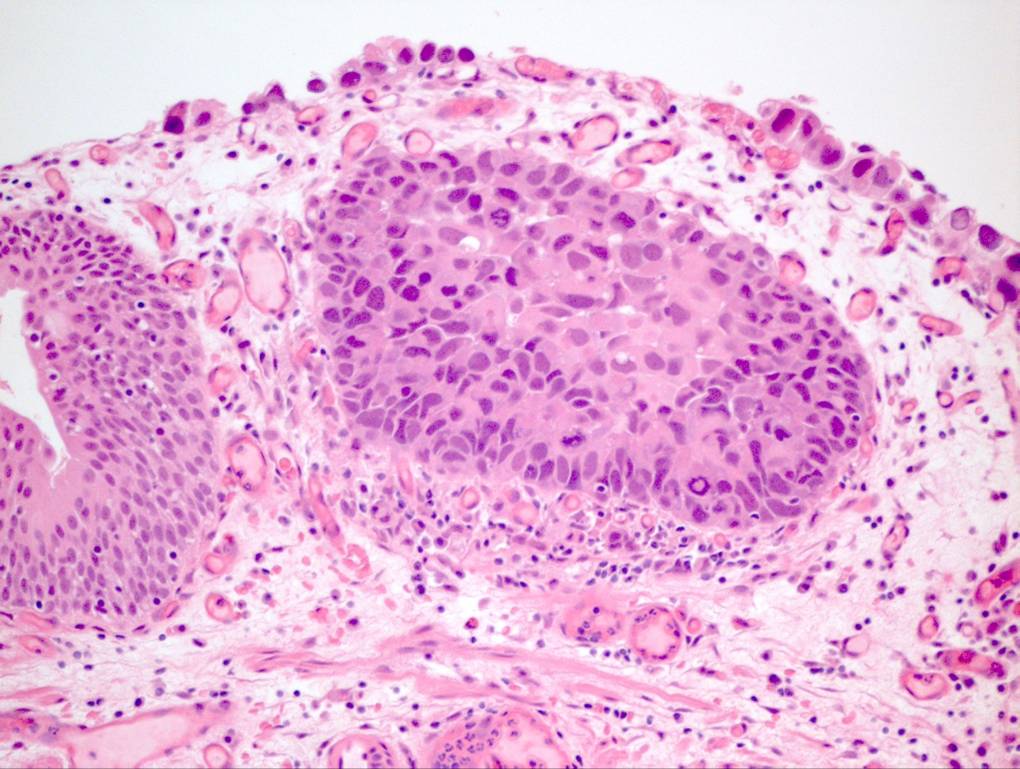

Bladder Flat Lesions

Case ID: 60

Reactive atypia

Atypia/dysplasia

Carcinoma in situ (CIS)